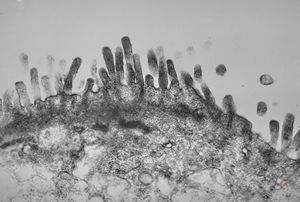

normal mucosa - jejunum - microvilli(anchored core rootlets)

normal mucosa - jejunum - microvilli